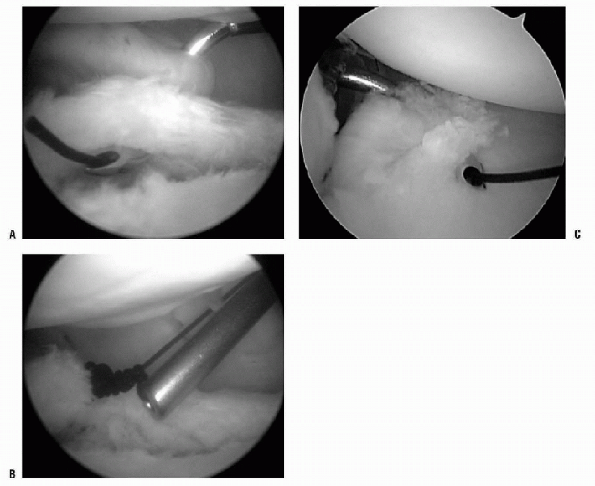

Figure 17-13 A: Suture-shuttling device demonstrating the pinch-tuck technique 1 cm from the labrum with an angled crescent hook. B: Suture has been shuttled for plication with monofilament suture. Nonabsorbable suture can be shuttled and tied for plication. C: Example of inferior plication from the posterior portal with viewing from the anterior-superior portal.

|